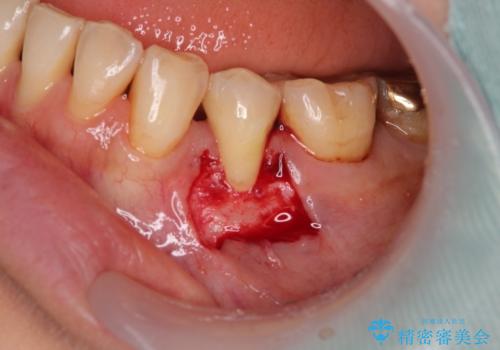

口蓋(上顎の内側)から採取した結合組織(歯肉の内側の組織)を移植することによる、根面被覆術を行うこととしました。